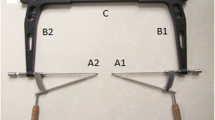

The statistical analyses showed no significant differences between males and females regarding all the above parameters but the OD value (Table 1). However, considering there is a safe area wide enough for screw insertion in the posterior column, we neglected the difference in the OD value between males and females. Therefore, mean parameters of OD and DG lengths, angle α, angle β, and the radian of the PG arcuate edge were used for the design of an adult universal guide template. The design of the optimal path of antegrade lag screw was conducted using UG 6.0 software in the 3D reconstruction models of the right hemipelvis. The inner side of the template, which was also the side in touch with the bone surface, was designed according to the extracted anatomical data of the quadrilateral surface and the iliac fossa. We designed one additional entry point on either side, 8.0 mm away from the optimal screw entry point. The two additional side entry points were designed to provide two more alternatives that can be chosen for accurate screw insertion or for need of insertion of one more screw. In addition, placement of three guiding needles (Kirschner wire) before insertion of the antegrade lag screw can help stabilize the guide temple closely onto the two bone surfaces. Consequently, digital design of a 3D guide template universal for Chinese adults with three orientation entry points was completed for the placement of lag screws into the posterior column of the acetabulum. The three orientation entry points at the guide template labeled as 1, 2 and 3 (Fig. 2) from the anterior to the posterior on the AP view indicated the first, second and third screw entry points on the acetabulum respectively. The digital template was then imported into the 3D reconstruction model of the right hemipelvis, which had been imported in .stl format into UG software. In the 3D reconstruction model, the template which was made attaching closely the quadrilateral surface was rotated in all directions to observe the fitness of the three screw paths to the posterior column of the acetabulum. After fine fitness was determined, a synthetic guide template for the left hemipelvis was manufactured by stereolithography apparatus (SLA) with light-sensitive resin (Fig. 2). The synthetic guide template for the left hemipelvis could be manufactured in a similar manner.

a Three-dimensional imaging of the navigation template. b The matching accuracy of template and the posterior column of acetabulum. the solid model of navigation template was manufactured by stereolithography apparatus (SLA) with light-sensitive resin. c The guide template was placed in the area of quadrilateral. d The three orientation entry points at the guide template, labeled as 1, 2 and 3 from the anterior to the posterior on the AP view, indicated the first, second and third screw entry points on the acetabulum, respectively